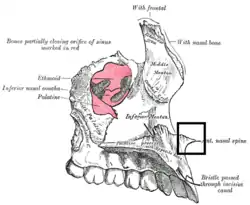

Left maxilla. Nasal surface (anterior nasal spine labeled at bottom right) | |

The anterior nasal spine, or anterior nasal spine of maxilla, is a bony projection in the skull that serves as a cephalometric landmark.[1] The anterior nasal spine is the projection formed by the fusion of the two maxillary bones at the intermaxillary suture. It is placed at the level of the nostrils, at the uppermost part of the philtrum. It rarely fractures.[2]